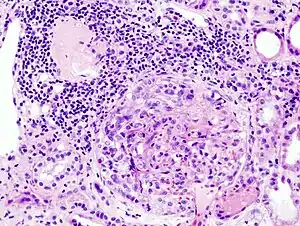

| Histopathological image of crescentic glomerulonephritis in a person with MPO-ANCA positive rapid progressive glomerulonephritis. Hematoxylin & eosin stain. | |